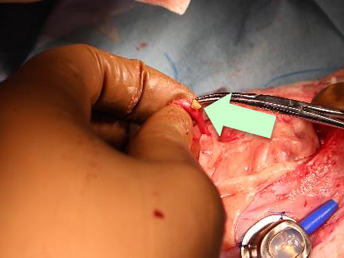

尿管結石を全て取り除くため、尿管の再建手術が必要になりました。

尿管をつなぎ合わせました。髪の毛より細い糸でつなぎ合わせます。

左右の尿管結石が同時に詰まってしまい左の尿管が破裂(矢印)していました。

漏れている左尿管を修復しSUBシステム2.0を左右の腎臓に装着しました。